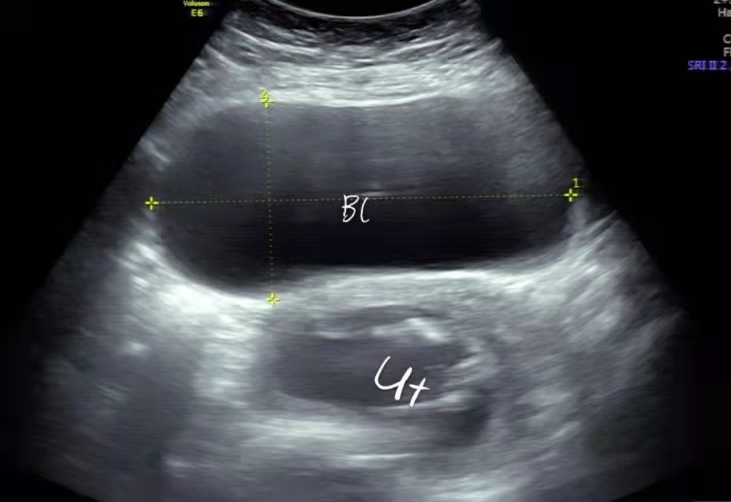

膀胱明显充盈表现细长,后方见妊娠子宫回声